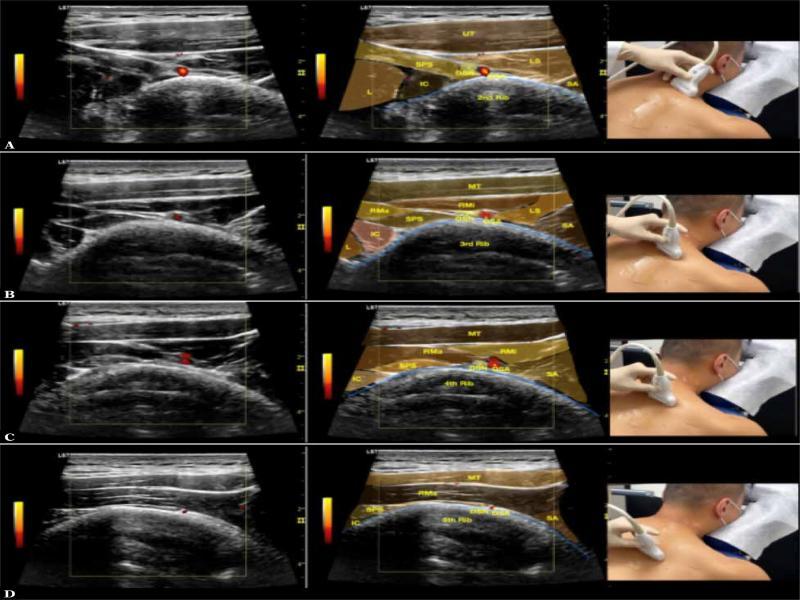

Fig. 2.

Sonoanatomy of the dorsoscapular nerve (DSN) and its relationship with the dorsoscapular artery (DSA) and other muscles from the second rib (A), third rib (B), fourth rib (C) to the fifth rib (D). UT – upper trapezius; SPS – serratus posterior superior; LS – levator scapulae; L – longissimus; IC – iliocostalis; SA – serratus anterior; RMa – rhomboid major; RMi – rhomboid minor; MT – middle trapezius

In Fig. 1B of Sharma’s manuscript, the linear muscle anterior to the rhomboids, posterior to the other paraspinal muscles, and with the muscle fibers directly slanting across the image, should be the serratus posterior superior (SPS) muscle. (Fig. 1) The DSN runs down the medial border of the scapula, deep to the levator scapulae and rhomboids, and superficial to the serratus anterior muscle and the SPS(24). However, the label of the DSN has been placed anterior to the SPS. Anatomically, this hypoechoic echostructure, considering it to be a swollen nerve, should be the posterior ramus of the thoracic spinal nerve, which is commonly entrapped by the insertion of the SPS over the second to fifth ribs. If this was swollen posterior ramus of the thoracic spinal nerve, the diagnosis in the case report should have been notalgia paresthetica (NP), which is attributed to the entrapment of the T2–T6 posterior rami that supply cutaneous innervation to the area(5). Additionally, the patient was treated with ultrasound-guided hydrodissection of the lateral branch of the posterior ramus of the thoracic spinal nerve. Herein, we provide a picture (Fig. 2) showing the sonoanatomy of the DSN in relation to the SPS, levator scapulae (LS), rhomboid minor (RMi), rhomboid major (RMa), and the levels from the second rib to the fifth rib. We also provide a video showing the scanning of these structures in Video 1.

Although we are delighted to see the use of the hydrodissection technique in this case report, we are worried about the fact that the intercostal muscles have been included as the sonolandmarks in the image before hydrodissection. The pleura and lung are located just below the innermost intercostal membrane, such that if the needle tip is not well visualized during hydrodissection, the needle may end up entering the lungs and causing pneumothorax. Instead, we highly suggest the use of the rib and insertion of the SPS as the landmarks; moreover, the final position of the needle and the final target of hydrodissection should be posterior/superficial to the SPS insertion and medial to the dorsoscapular artery, with the rib and needle tip always in view to prevent entry into the lungs (Video 2).